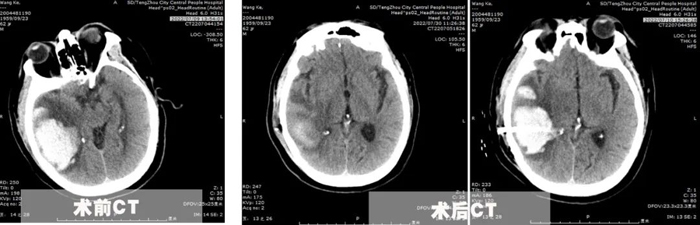

患者王先生,62歲,體重200余斤,糖尿病、冠心病、腦梗塞病史3年余,長期口服二甲雙胍、阿司匹林、瑞舒伐他汀等藥物,病情控制一般。7月8日,患者突發(fā)頭痛頭暈,出現(xiàn)一側肢體偏癱、意識障礙,急診行顱腦CT提示枕頂葉大面積腦出血,血腫量超過50ml,有手術指征。

為了在最恰當?shù)氖中g時機及時完成手術,7月10日,李永濤主任放棄在家休息的時間,帶領陳凡宇主治醫(yī)師,在局麻下為患者完成顱骨鉆孔腦出血引流術。術中僅在切口線注入5ml利多卡因,然后顱骨鉆孔形成直徑約1cm骨孔,切開硬腦膜后精準置入直徑約5mm的硅膠引流管于血腫腔,術后復查CT并引流管內注入尿激酶促進血腫引流。經(jīng)過3天的引流,血腫基本排除,腦壓下降,癥狀改善。同時盡早給予患者床旁肢體功能康復,并積極調整患者血糖、血壓、及心臟功能,給予患者精神鼓勵和心理輔導?;颊叱鲈旱臅r候已經(jīng)能夠獨立行走,生活自理。